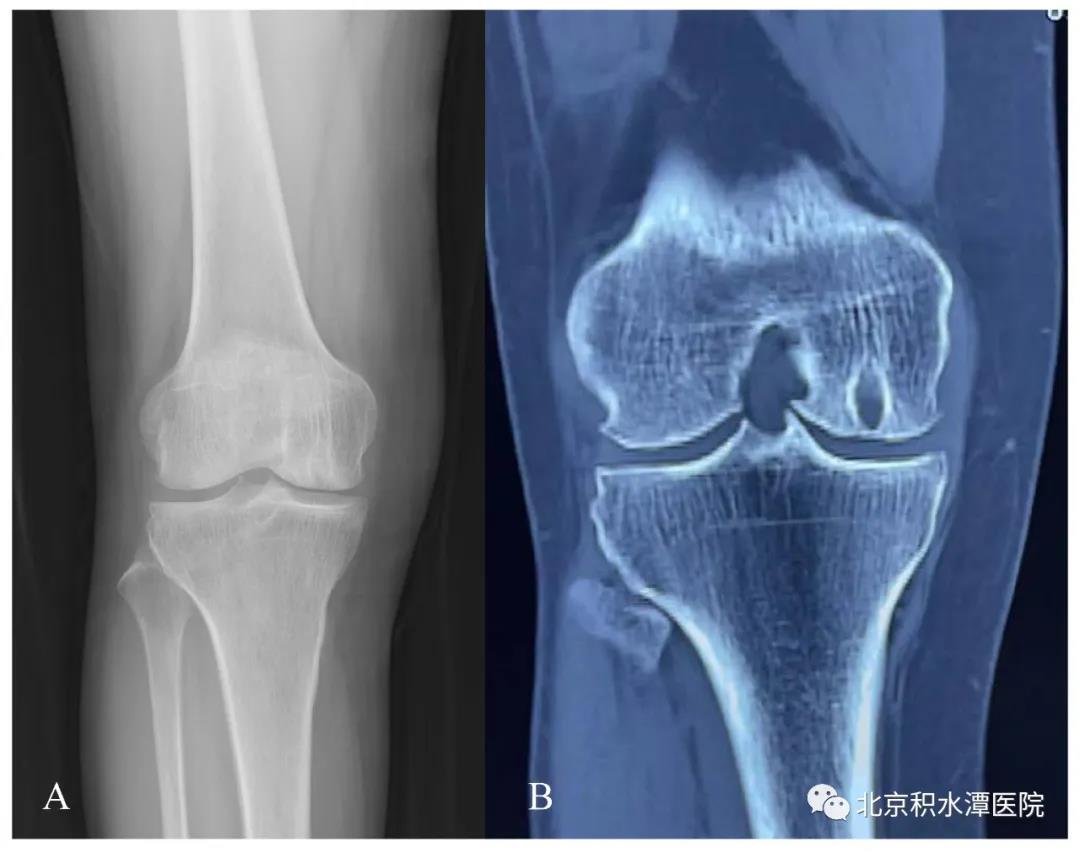

患者术前右膝关节X光(A)及CT(B),提示右膝关节股骨内侧髁局限性骨缺损病变,关节间隙情况良好。